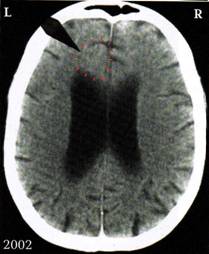

3. ábra:

A mellékelt felvételen az alacsony cukorközpontban láthatjuk a Hameri gócot (= „ellenszegülés-konfliktus” a balkezes nő esetében), mely 17 éves korában keletkezett a parkban, amikor szexuális (orális) erőszakot követtek el ellene. Egészen tavalyig még farkaséhsége volt.

Ehhez az „ellenszegülés-konfliktus”-hoz kapcsolódik a „HIV-smegma-konfliktus” (= smegma-allergia).

4.ábra: Tisztán kivehető az alacsony cukorközpontban található Hameri góc („undor/félelem-konfliktus), mely az orális nemi erőszak során keletkezett.

Tisztán látszik a (sötét) kaverna. A hozzá tartozó tumor 4 éven keresztül növekedett (1996-2000). Miután éjszakánként a páciens immáron 2 éve rendszeresen verejtékezik és köhög, felfedezték nála a tuberkulózist és kezelték. Itt látható bal oldalt annak maradványa.

A bal oldali Hameri góc a ponsban a bal tüdőlebenyhez tartozik (most már kaverna, ezt megelőzően szoliter tüdőhólyagocska sejtszaporulat volt).

A középső, jobb oldali koponyagödörben található az „esés-konfliktus” során keletkezett Hameri góc (amikor megütötte a fejét az ugródeszkába az uszodában). A kettő között látható a jobb vesegyűjtőcsatorna reléjén fekvő Hameri góc („lét-konfliktus”, oliguria).

A jobb (látszólag nem feltűnő) vese az, amely reléjén az aktív Hameri Góc becsapódott és amelyik visszatartja a folyadékot (oliguria). Ez esetben egy „lét-konfliktus” áll fenn, mert a páciens most egy nigériai férfivel él együtt, akitől egy újabb gyermeke született. Létminimumon él, míg azelőtt megengedhette magának, hogy szórja a pénzt.

A bal vesének (l. nyíl) ún. tágult vesemedencéje van, ez a bizonyíték arra, hogy ott már lezajlott egy vesegyűjtőcsatorna-tuberkulózis folyamat.

Ezeken az ábrákon ugyanaz a bal oldali tágult vesemedence látható horizontális metszetben.